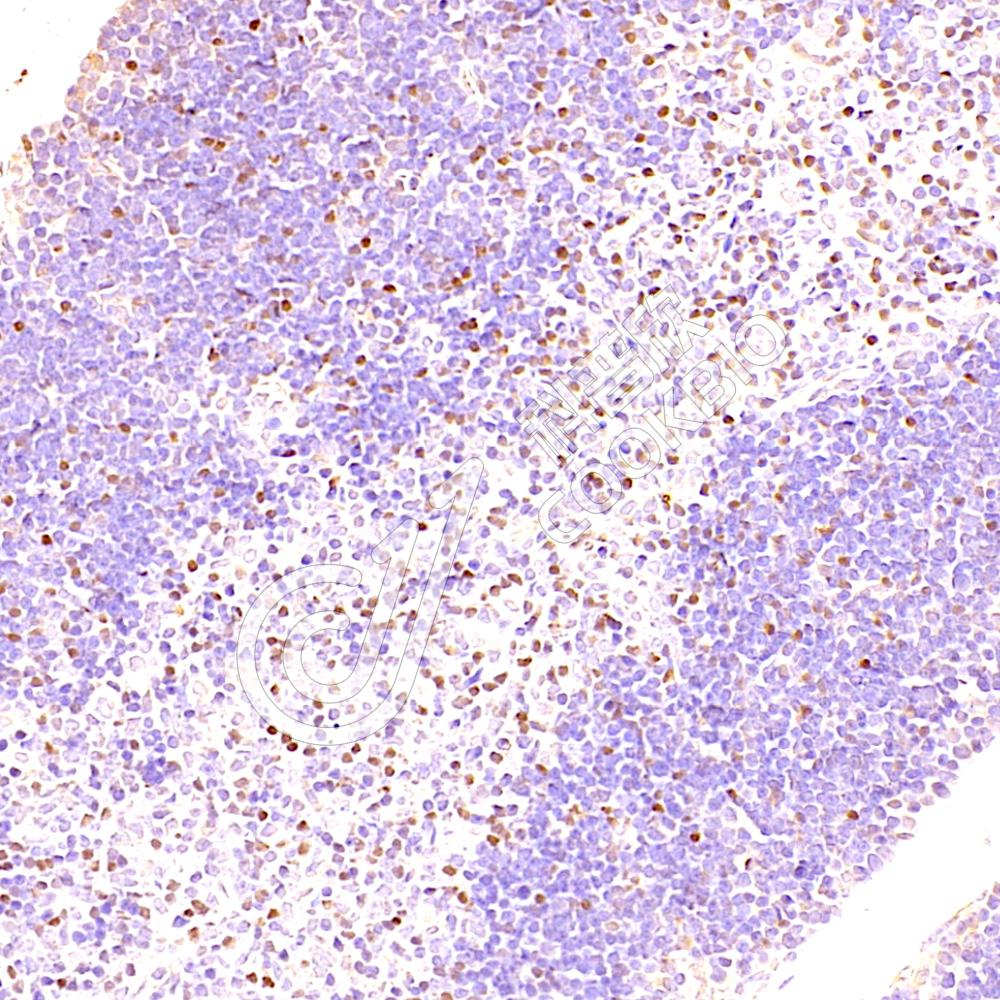

IHC检测TOX蛋白(货号 K1338361).

样品: 小鼠胸腺, 4%多聚甲醛 (货号KSG1101) 固定12-24小时.

抗原修复: Tris-EDTA抗原修复液(pH 9.0) (KSG1203), 98℃, 20分钟.

—抗: 1: 3000稀释, 4℃ 孵育过夜.

二抗: S-vision免疫组化多聚二抗(山羊抗兔),即用型 (货号KB3906), 室温孵育20分钟.